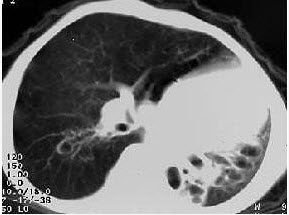

女,8岁,如图所示,最可能的诊断为()

A . 左下肺不张

B . 左下肺隔离症

C . 左肺发育不全

D . 左下肺支气管扩张

E . 左下肺支气管囊肿